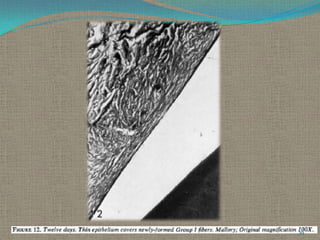

12 Days.

The sulcular epithelium remains thin and is located at the cementum enamel

junction. Keratinization is present at the margin where the sulcular and oral

epithelium join. There is no inflammatory infiltrate

in the connective tissue which underlies the newly

formed sulcular epithelium. It is well collagenated,

and Group I fibers as well as the subsulcular capillaries

show some semblance of organization.

The tip of the margin is well vascularized